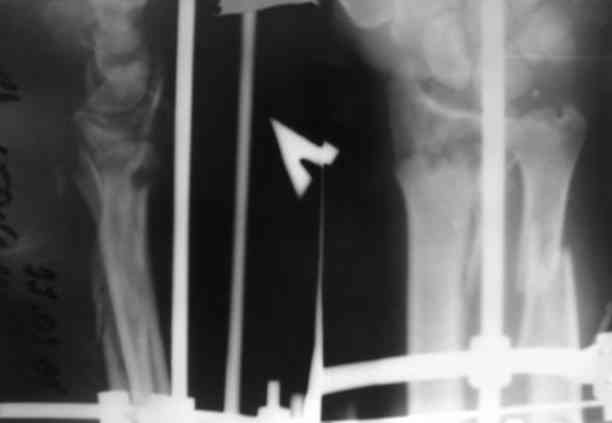

Уважаемые участники форума,поделитесь опытом... Поступил больной 23.03.07 в отделение нейрохирургии с диагнозом:кататравма, ушиб головного мозга ср.тяжести,линейный перелом лобной кости слева, открытые переломы костей обоих предплечий.

По дежурству перооперирован.На оба предплечья наложены ЧД аппараты (см. приложение) Через 3 дня переведен в травм.отделение. Мнения коллег о дальнейшей тактике разделились: накостно с трансплантацией или ЧДО аппаратом Илизарова, с целью добиться, хотя бы относительно удовлетворительного стояния.На сегоднешний день выраженный болевой синдром, больше слева.Раны на предплечье заживают первично.